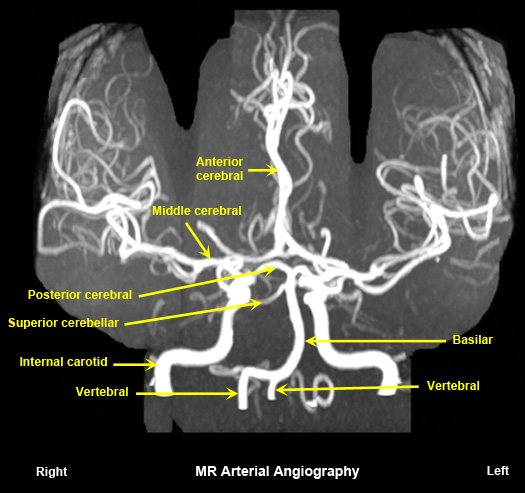

Normal MR arterial angiography

No radiation.

Contraindicated when there are metallic objects in the critical sites. |